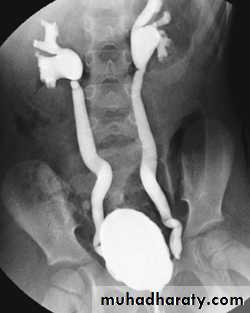

Vesicoureteric Reflux

Abnormal valve mechanism at UVJ resulting in reflux, ureteral dilatation, clubbed calices, eventual renal scaring.Clinical presentation: recurrent UTI, if long standing lead to renal scarring.

Two Types:

A. CONGENITAL REFLUX = PRIMARY REFLUX

Occurs in children, due to short submucosal ureteral tunnel, unilateral or bilateral.

Resolve spontaneiusly.

B. ACQUIRED REFLUX = SECONDARY REFLUX causes:

1. Duplication with ureterocele.2. Cystits.

3. Urethral obstruction.

4. VU reflux.

Diagnosis:

Mainly by voiding cystourethrography( VCUG) by urinary bladder catheterization and distension to confirm reflux.Also by US for assessment of renal parenchyma and scarring.

Primary VUR